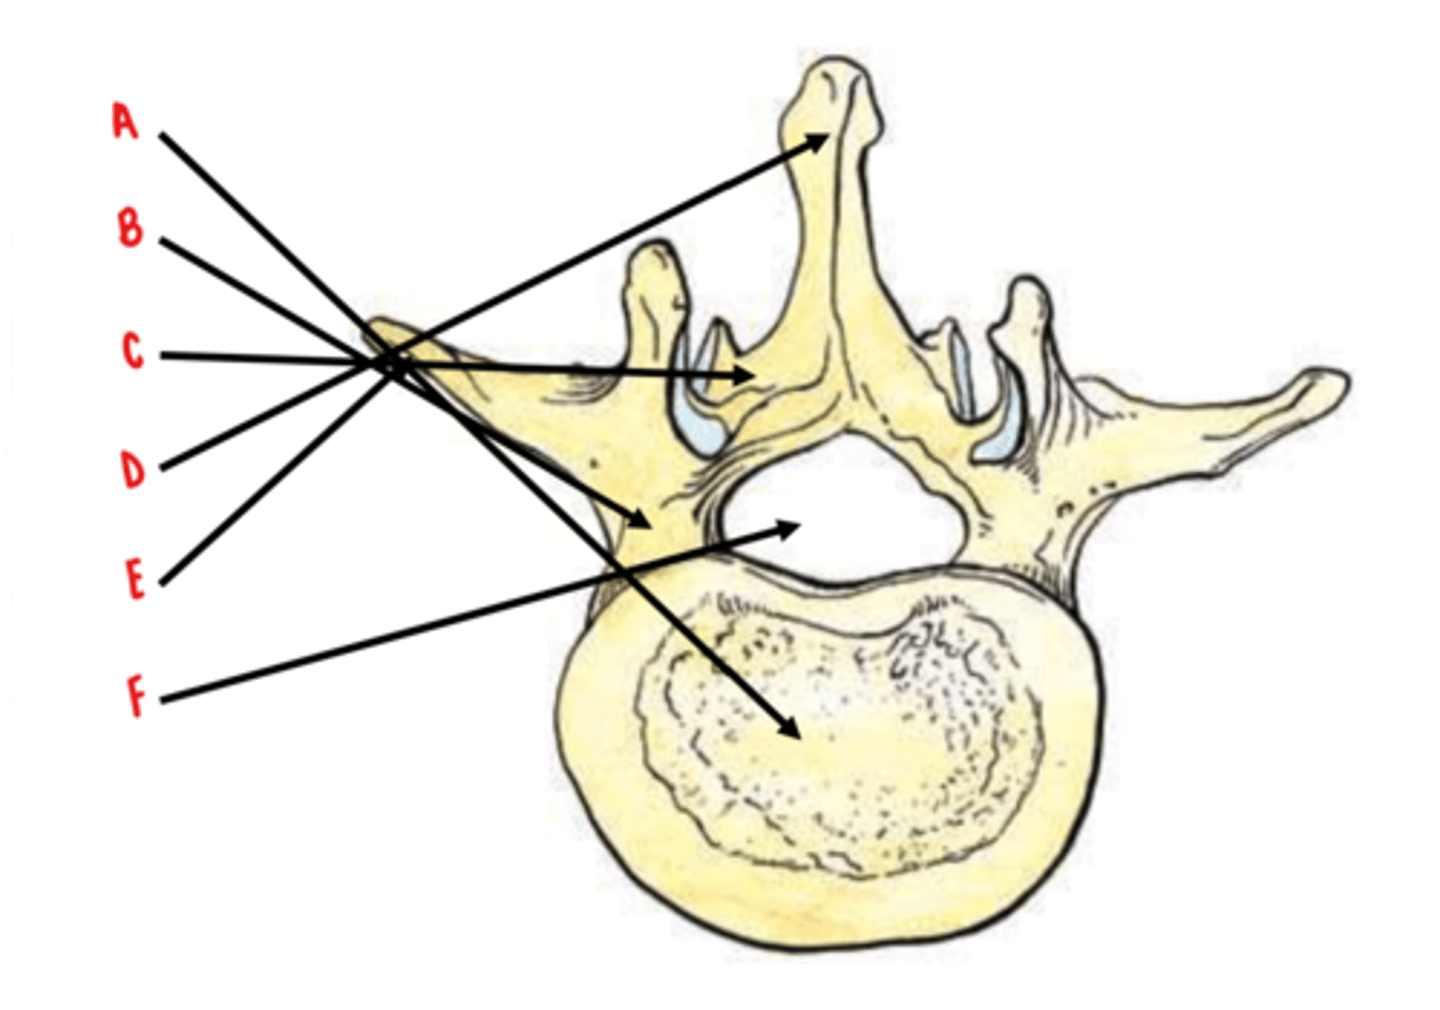

body

Identify A

pedicles

Identify B

laminae

Identify C

spinous process

Identify D

transverse process

Identify E

vertebral foramen

Identify F